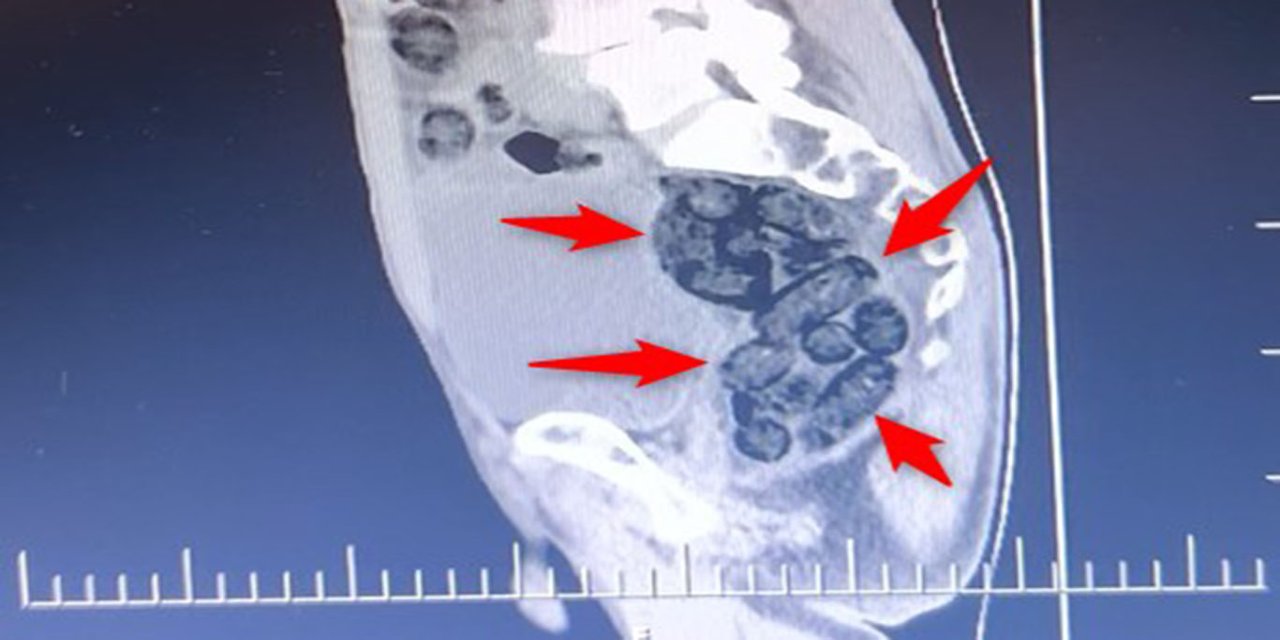

Otobüste yakalanan şahsın midesinden metamfetamin çıktı